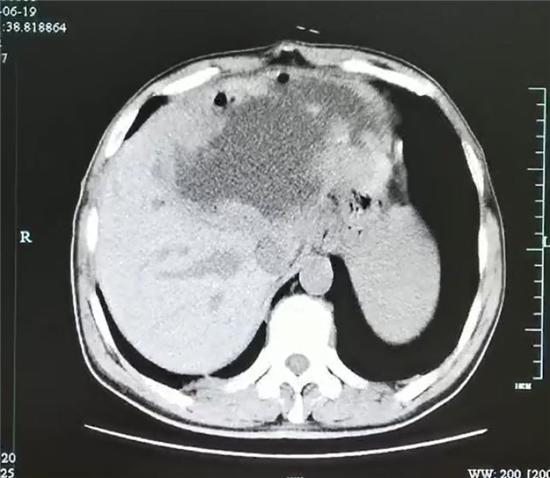

经过三周的引流和保守治疗,复查增强CT发现脓肿小了一大半,但是肝脓肿厚壁及厚壁上的很多肿瘤样组织没有变化,引流管里引流出来的液体开始减少,而且脓腔也不再进一步缩小,显示出这个脓肿很难自愈。

引流后脓腔有所缩小,但厚壁及壁上的肿瘤样的结构更加明显。